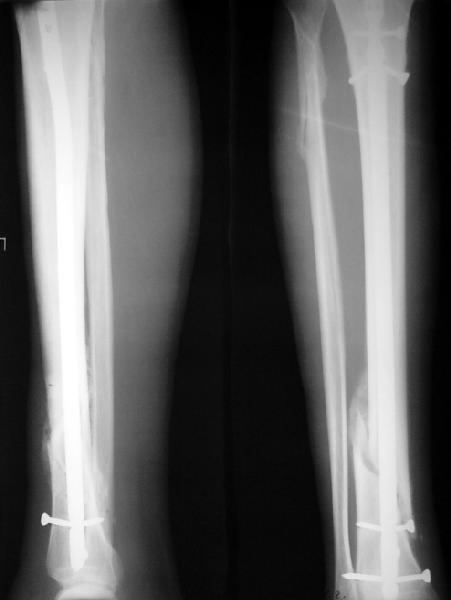

На мой взгляд, на снимках, приведённых Вами - неправильно сростающийся перелом дистальной трети большеберцовой кости, состояние после остеосинтеза интрамедуллярным гвоздём.

Вы не послали послеоперационный снимок, поэтому трудно судить о состоянии редукции после операции.

Установка с медиальной стороны гвоздя в области дистального фрагмента дополнительного шурупа помогло бы Вам репонировать и удержать перелом в анатомическом положении, предотвратило варусную деформацию и смещение по ширине.

Let to express concerning technique of operation my opinion... Insertion of a screw to medial side of a nail in distal fragment would help you to reduction and to keep this fracture in anatomic position has prevented varus deformity and displacement on width. By the way, if it is possible send a postoperative picture.